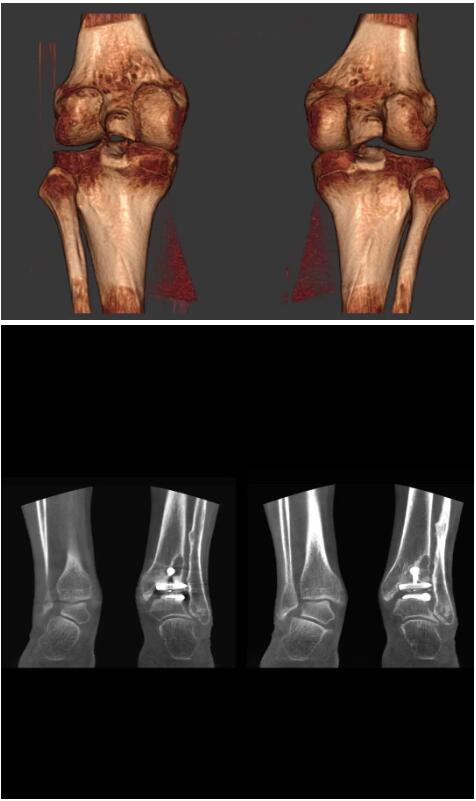

以下是這些“特立獨行”的CT所拍出來的圖像: